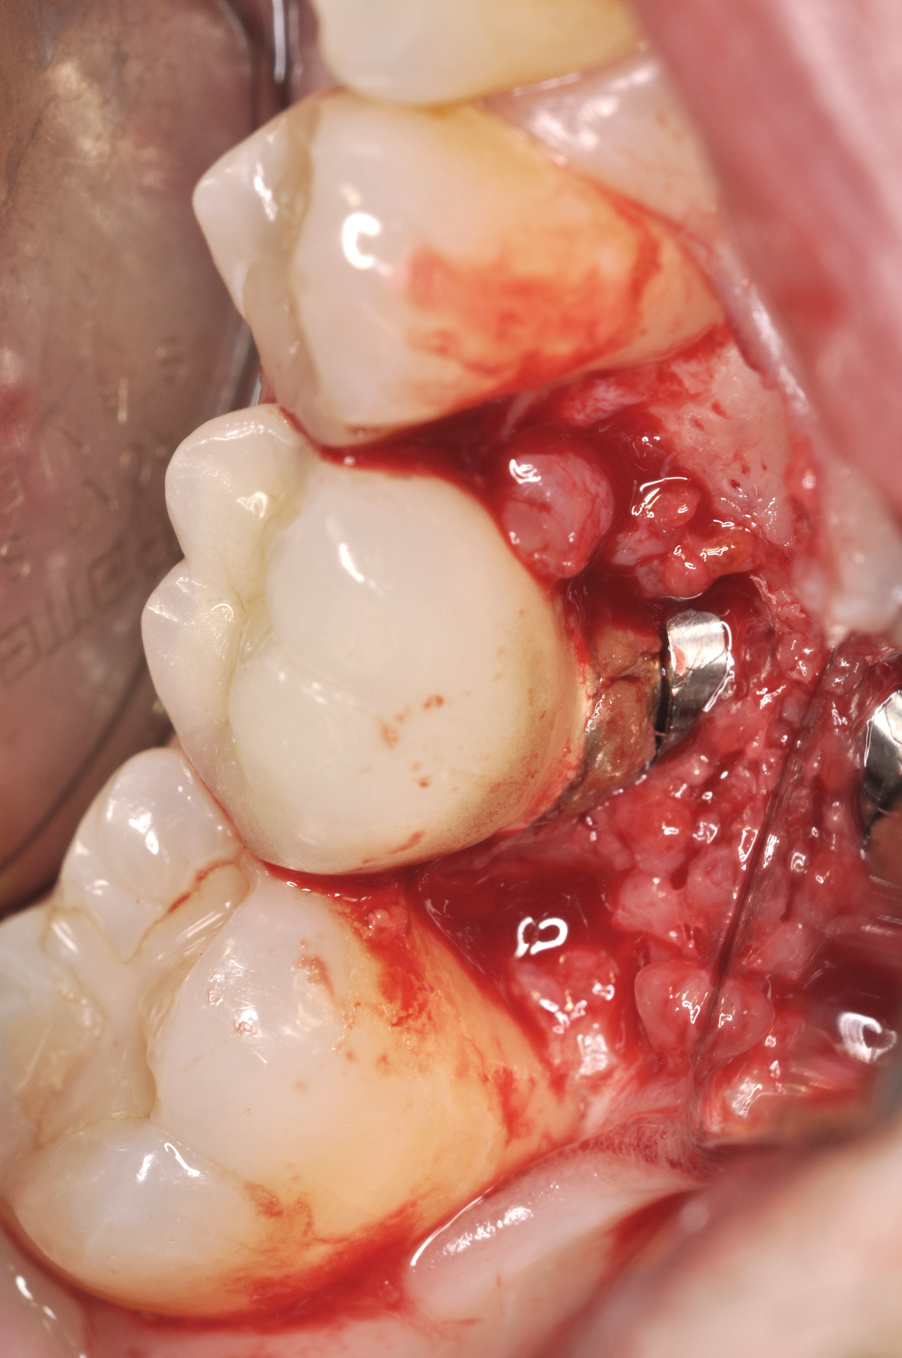

Fig 8. Loss of restoration and subsequent tissue overgrowth from broken abutment screw as shown in the radiograph (Fig 9).

Figure 8

Fig 9. Radiograph depicting fractured screw inside of the implant.

Figure 9